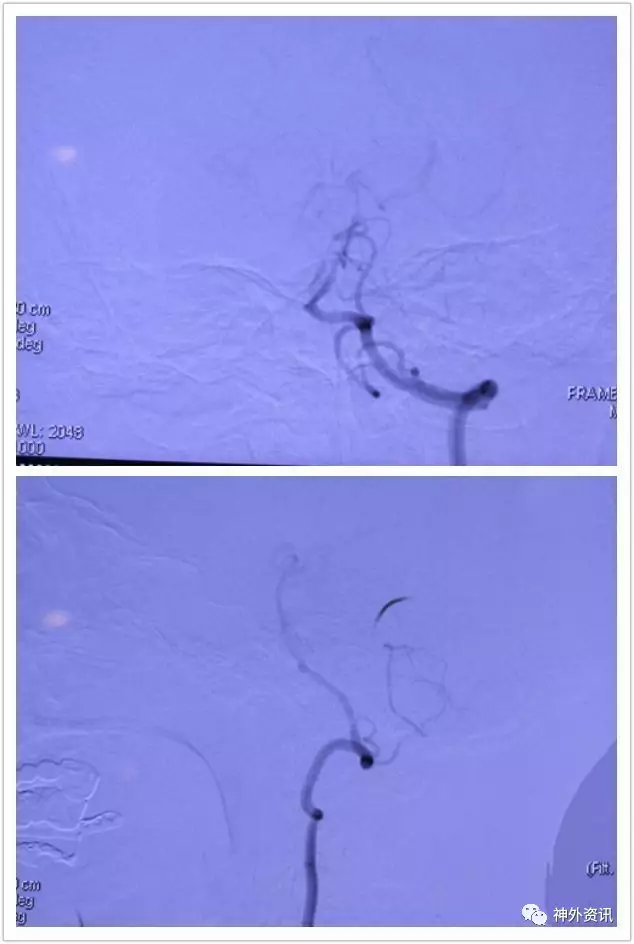

正位造影看不到左ⅤA,开口段内膜过度增生闭了

L-VA晚间可见肌支吻合与VA相通,闭塞节段限于开口段,可否一试把支架与增生内膜斑块取了再通呢?

既然DSA提示L一VA远端肌支吻合血管供血有显影,病人有确切临床症状,这个病人有指征也有再通的可能。